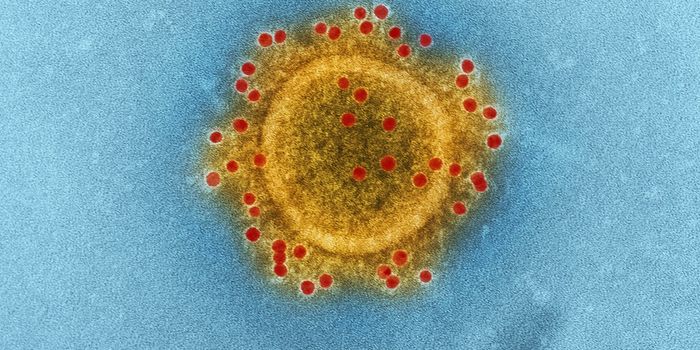

FEB 08, 2020MicrobiologyIn China, authorities are still struggling to contain the new coronavirus that emerged in the city of Wuhan and has sinc ...

APR 27, 2020MicrobiologyThe pandemic virus that causes COVID-19 has now infected nearly 3 million people, and killed over 200,000.

MAY 10, 2021MicrobiologyThe pandemic virus SARS-CoV-2 has changed the world in devastating ways, taking hundreds of thousands of lives & new var ...

MAR 03, 2020MicrobiologyThere have now been nine deaths in the United States, all in Washington state from COVID-19, the illness caused by the n ...

NOV 01, 2020MicrobiologySARS-CoV-2, which causes COVID-19 has to get into cells to cause infection. It does so with a spike protein on its surfa ...

AUG 14, 2020Cell & Molecular BiologyThere are several coronaviruses that we know about, and they cause a wide range of illnesses. Some, like SARS-CoV-2, are ...